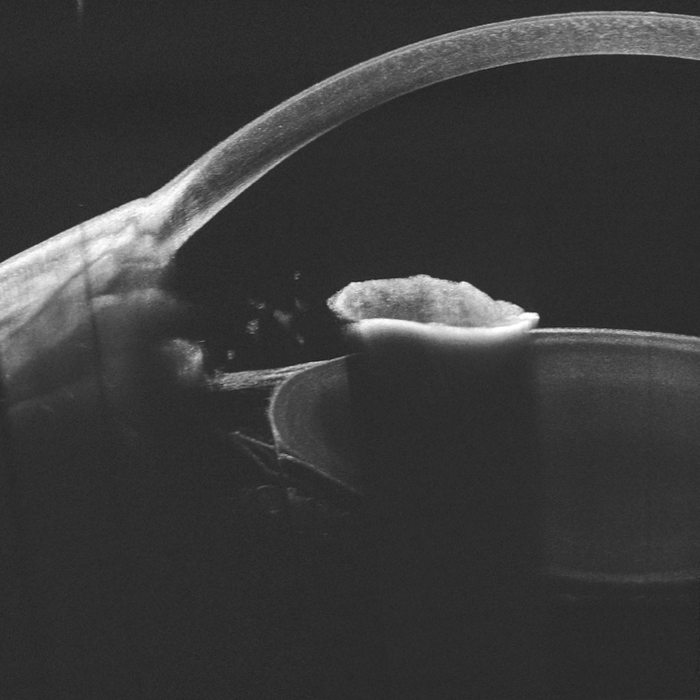

Uveitída - synechie po zápalových procesoch v oku

Synechie, zrasty dúhovky k rohovke alebo šošovke, zachytené pomocou Intalight DREAM OCT.